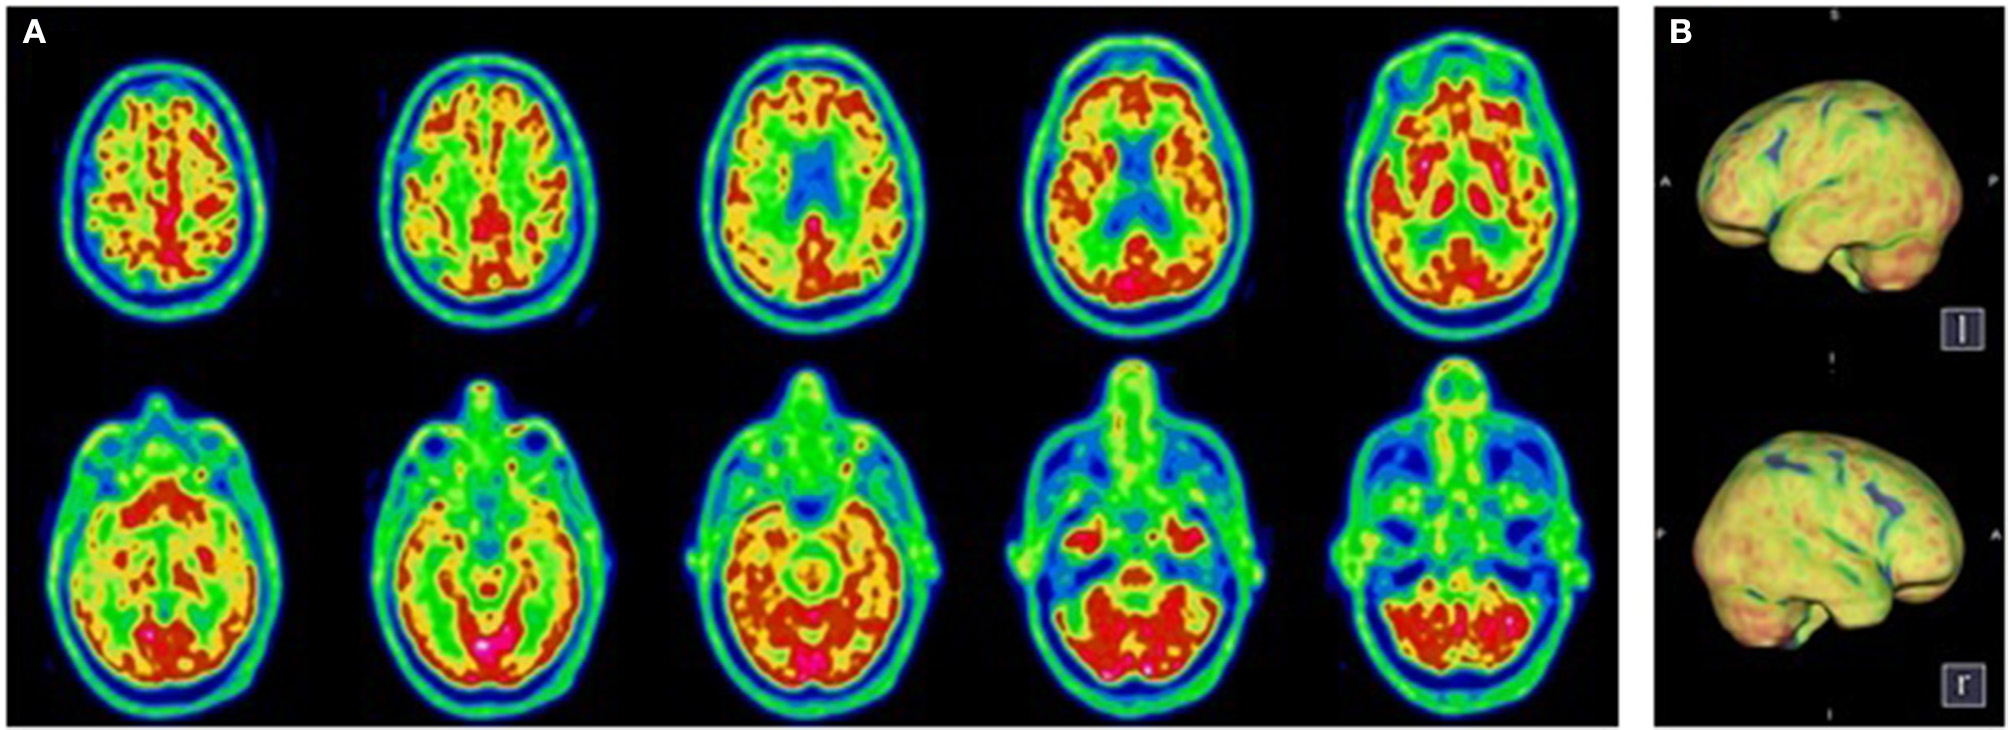

Figure 1

Transaxial (A) and Volume Rendered Brain (B)18F-FDG PET. Diffuse cortical hypometabolism. Normal metabolism of the sub-cortical structures and the cerebellum.

A 78-year-old patient without psychiatric or oncologic history was admitted to the ICU with severe acute respiratory distress syndrome (ARDS) due to SARS-CoV-2 infection and needed endotracheal intubation for 25 days. He received hydroxychloroquine for 5 days and after extubation, the sedation was withdrawn. Two experienced physicians clinically assessed the patient at 7 days post-sedation withdrawal as he presented a pathological awakening with absent external responsiveness to stimulation and facial akinesia. According to the French version of the Coma Recovery Scale–Revised (16), he was classified as having unresponsive wakefulness syndrome (UWS) (Table 1). However, the MBT-r assessment categorized him as presenting with clinical cognitive motor dissociation (cCMD) with clear, subtle signs of conscious perception not considered by the CRS-R (i.e., attempt at visual pursuit, intentional defense gesture on painful simulation of the breast and an associated grimace). A routine electroencephalogram (EEG) ruled out a non-convulsive status epilepticus. Brain MRI was normal. The lumbar puncture was traumatic with 320 erythrocytes/mm3, without pleocytosis (<1 cell/mm3), normal lactate (2.28 mmol/l), a slightly diminished glucose ratio (0.39), the presence of oligoclonal IgG bands, which were identical in the serum and the CSF indicating rupture of the blood brain barrier consistent with systematic infection, negative SARS-CoV-2 and viral/bacterial pathogen PCR and normal ß-Amyloid (-42), hTau and Phospho-Tau (181P) levels. A brain 18F-FDG PET showed diffused hypometabolism of the cortical and subcortical regions of the two cerebral lobes, sparing partially the occipital cortex, the basal ganglia and the cerebellar cortex (Figure 1). Patient evolution was marked by a fluctuating hyperactive delirium treated by quetiapine, clonidine and melatonin. He was transferred to the internal medicine ward. His neurological symptomatology gradually improved. He regained voluntary control of his motor responses and followed simple commands, reaching the CRS-R criteria of recovery of consciousness. The overall swift rate of motor interaction recovery along with functional improvement, confirmed the preserved cognition as expected in CMD condition. The patient was transferred to a neuro-rehabilitation clinic, 44 days post-admission with a Glasgow Outcome Scale of three (indicating severe disability). He underwent neurorehabilitation for another 14 days attaining a Glasgow Outcome Scale of 4 (indicating moderate disability) and was able to return home to his wife.

Consistent with these data, our hypothesis is that for the two patients, SARS-Cov-2 induced functional impairment in strategically localized areas of the executive motor network (i.e., frontal, pre-frontal). Indeed, the brain 18F-FDG PET in these patients showed a diffused hypometabolism, sparing the motor and pre-motor cortex but affecting the associative areas responsible for the integration of motor initiation and coordination, explaining the clinical picture.